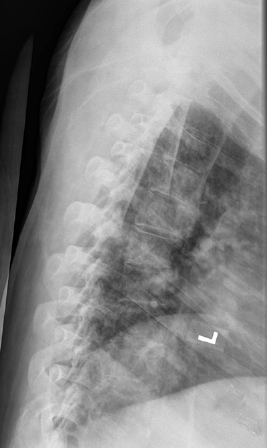

B

Image A shows our patient's lateral thoracic spine radiograph, performed for back pain. The spine is very washed-out in appearance and hard to see due to marked osteopenia. A normal comparison in a different patient is shown in Image B, where each vertebra and disc space can be clearly seen. Radiography cannot quantify the degree of bone loss, but can detect overall decreased density as well as comlications, like compression fractures. For quantification, bone densitometry is indicated.